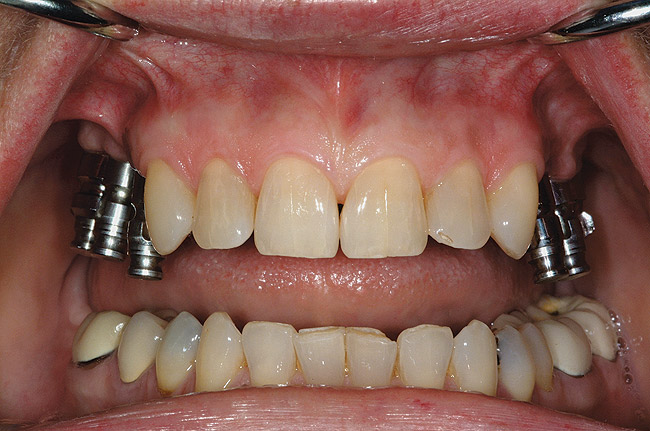

Figure 2  Removable prostheses can provide proper support and enhance overall facial esthetics for the patient.

Figure 2

Figure 3  Removable prostheses can provide proper support and enhance overall facial esthetics for the patient.

Figure 3

Many factors must be considered for dental implants;8 however, one of the most crucial is an accurate diagnosis. There may be several treatment options for partially or completely edentulous cases, but for each patient there is only one diagnosis. Care should be taken to adequately evaluate the patient before weighing treatment options (Figure 1). Several important considerations are the completion of growth in a young patient,9 health status in a more mature patient,10 the patient's financial concerns, and time constraints in completing the proposed treatment. In addition, patient expectations should be fully reviewed prior to initiating treatment: patients must have realistic expectations and understand the type of prostheses that can be fabricated for their particular treatment needs (Figure 2 and Figure 3). When the evaluation is complete, multidisciplinary treatment planning that includes the laboratory technician, implant surgeon, orthodontist, and the restorative dentist should be considered. A comprehensive case presentation should then be completed with the patient to discuss all options, including no treatment. A written summation of the treatment plan11 and informed consent are then provided to the patient to review and accept before treatment commences. The restorative dentist must initiate the process in determining the prosthesis design and coordinate the treatment sequence with the other dental professionals. While traditional treatment planning has been the standard, the advent of cone beam computed tomography (CBCT) has allowed 3-dimensional planning, which offers more comprehensive information to be supplied to the patient prior to any surgical procedure and which can greatly enhance the outcome.